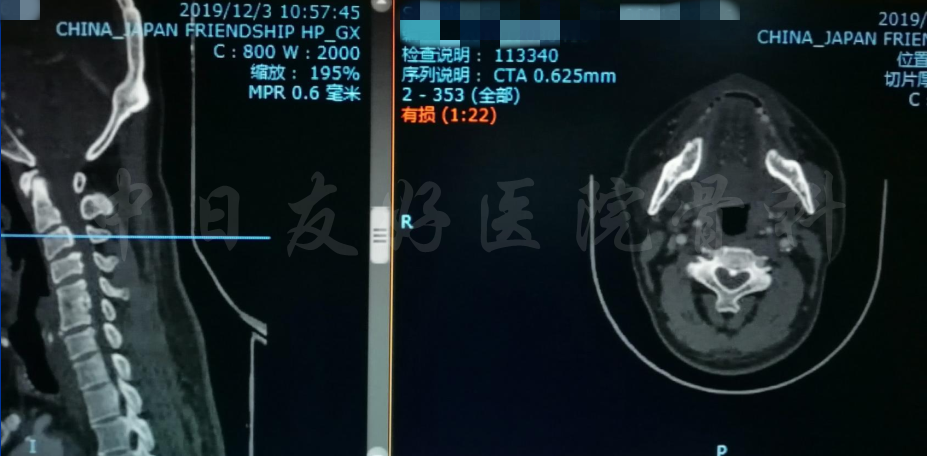

影像学检查

颈椎X片

颈椎MRI

颈椎MRI

颈椎各节段MRI(上下滑动)

颈CT(上下滑动)

腰椎MRI